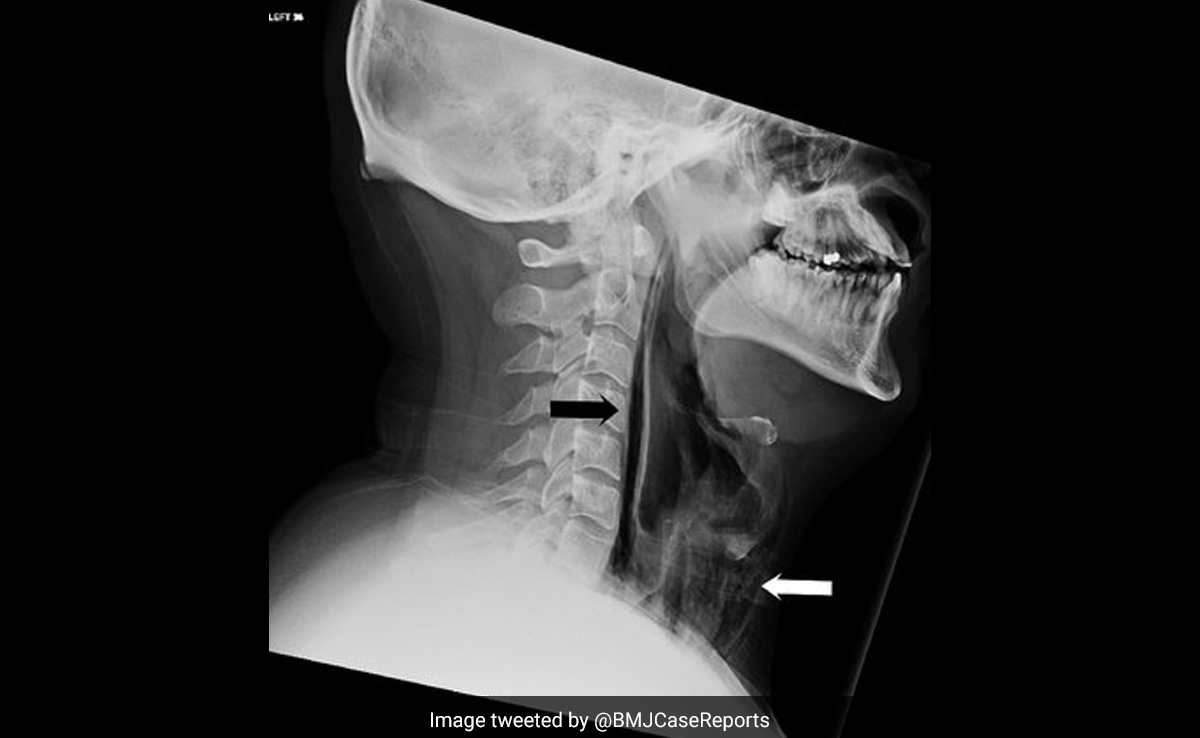

A British man injured his throat because he held in a powerful sneeze. According to a paper published in BMJ Case Reports in 2018, a 34-year-old man attempted to suppress a sneeze by clamping his mouth shut and blocking both nostrils, but the force of the sneeze ruptured his throat.

He started to have strange symptoms including painful swallowing, a change in his voice, and a popping sensation and swelling in his neck. He decided to seek medical attention.

The doctors said that streaks of air had become trapped in some of his throat tissue and ruptured his throat. Spontaneous rupture of the pharynx is very rare, usually caused by vomiting, retching, heavy coughing or some kind of trauma.